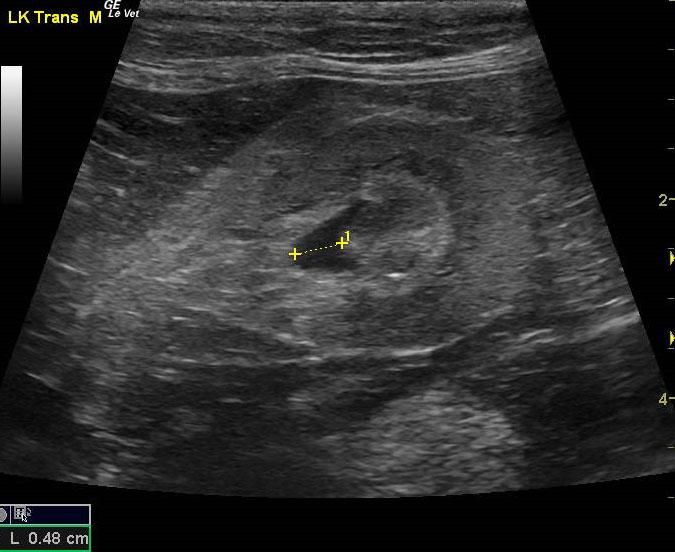

A 16-year-old spayed female cat was presented for evaluation of hematuria and inappropriate urination. On urinalysis, an inappropriate specific gravity (1.014) and hematuria were evident. The only abnormality on blood work was mild anemia.

A 16-year-old spayed female cat was presented for evaluation of hematuria and inappropriate urination. On urinalysis, an inappropriate specific gravity (1.014) and hematuria were evident. The only abnormality on blood work was mild anemia.